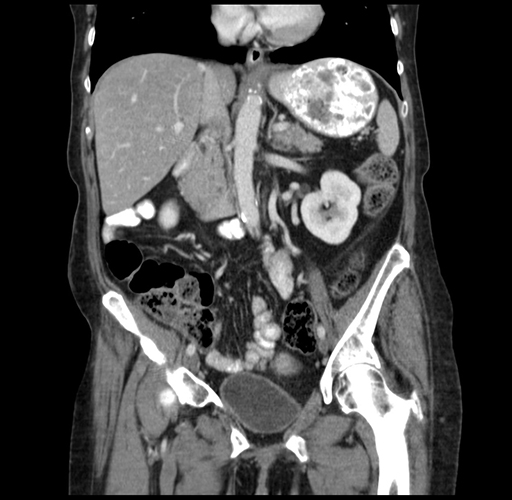

Axial Venous

Coronal Venous